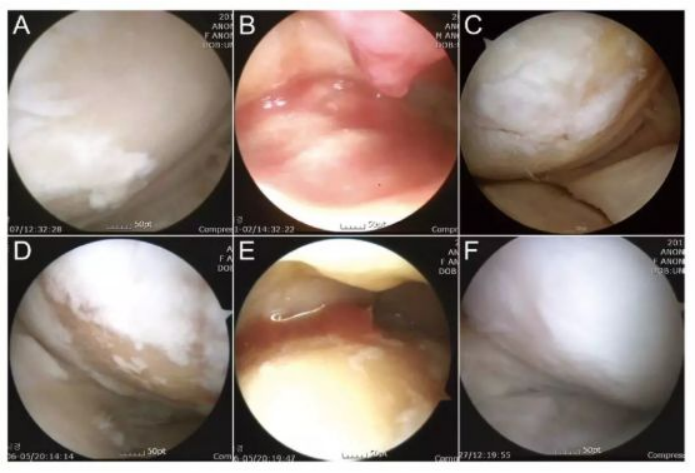

下图中A-C为51岁男性膝关节镜,,,D-F为54岁女性膝关节镜。。A/D为治疗前,,白色示意软骨,,浅黄色示意裸露的骨。。。B/E为间充质干细胞注射。。。C/F为治疗后的关节镜检查。。

·研究结果:ADSCs治疗后能够显著改善膝关节骨性关节炎,,BMI越高效果越差。。。